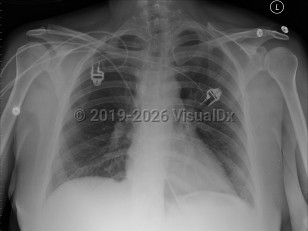

Congestive heart failureCongestive heart failure